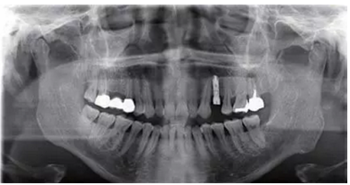

種植完成后可以通過拍攝曲面體層或是根尖片來確認(rèn)種植體的植入情況,并作為資料加以保存。

種植手術(shù)完成2周后進行拆線。可以看出軟組織愈合良好。

圖7 曲面體層片

圖8 拆線時的口內(nèi)照片